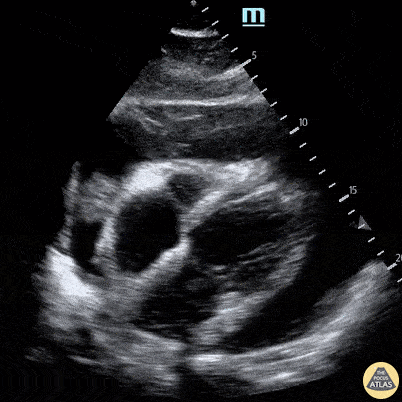

50 y/o male presented with 1 week of feeling generally unwell, tired and short of breath. Rapid atrial fibrillation was present in the department. POCUS performed demonstrating large pericardial effusion (note some evidence of diastolic collapse as well as partially complex-appearing pericardial fluid collection). Nishant Cherian Emergency Medicine Registrar